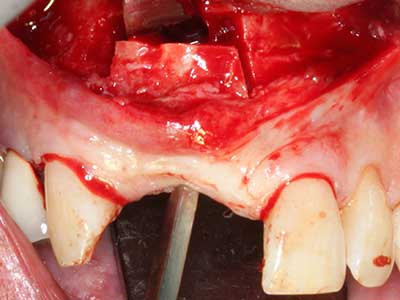

Bei der Knochenblockentnahme zeigen sich weitere Vorteile für die Piezochirurgie: Neben der bereits beschriebenen hohen Präzision bei der Osteotomie stellt sich gerade die Verwendung der dünnen Sägespitzen als besonders materialschonend heraus. Bei der Verwendung insbesondere von Lindemannfräsen sind mit deutlich höheren Entnahmeverlusten durch die dickere Instrumentenspitze zu rechnen (Lakshmiganthan, Gokulanathan et al. 2012). Die insbesondere bei retromolar entnommenen Blocktransplantaten notwendige basale Abtrennung wird durch speziell hierfür vorgesehene rechtwinklige Sägen erleichtert, so dass die Piezochirurgie als präzises, übersichtliches und sicheres Verfahren zur retromolaren Knochenblockgewinnung angesehen wird (Happe 2007) (Abb. 1-12).

Indikation: Bone Splitting

Knochengewebe ist nicht nur rein mineralisch, sondern auch in wesentlichen Anteilen aus Kollagenfasern aufgebaut. Dies gewährleistet neben einer guten Druckfestigkeit eine gewisse Flexibilität, welche für die Durchführung von Augmentationen genutzt werden kann. Bei der klassischen Expansionsplastik im Sinne eines Bone Splittings wird der atrophierte Kieferkamm in seiner Längsachse gespalten und nach Erreichen einer ausreichenden Osteotomietiefe vorsichtig aufgedehnt (Abb. 13-16), idealerweise ohne den Kiefer wesentlich zu deperiostieren (Brugnami, Caiazzo et al. 2014, Stricker, Fleiner et al. 2014). Bewährt haben sich Schrauben- und Plattensysteme mit zunehmender Expansionsdistanz, um die beiden Knochenlamellen unterhalb der Bruchschwelle voneinander zu distanzieren. In der Regel werden Restknochenbreiten von mindestens 3-4 mm gefordert (Chiapasco, Zaniboni et al. 2006), um eine ausreichende Flexibilität und knöcherne Bedeckung der einzubringenden Implantate zu gewährleisten. Ggf. kann eine ein- oder beidseitige vertikale Entlastungsosteotomie die Flexibilität verbessern. Als Alternative zur klassischen Technik wurde eine Kombination mit weiteren augmentativen Techniken vor allem auf der bukkalen Seite beschrieben.

Mittels Piezosägen erfolgt die Anlage des Splittings besonders schonend und ohne wesentliche Dimensionsverluste, so dass sich keine signifikanten Unterschiede von Implantaten im gesplitteten Kiefer im Vergleich zum nicht defizitären Alveolarkamm gezeigt haben (Chiapasco, Zaniboni et al. 2006, Danza, Guidi et al. 2009). Gerade beim lokal begrenzten und tiefen Splitting ist jedoch stets auf eine ausreichende Wasserkühlung zu achten, um thermische Belastungen in den apikalen Osteotomiebereichen zu vermeiden.